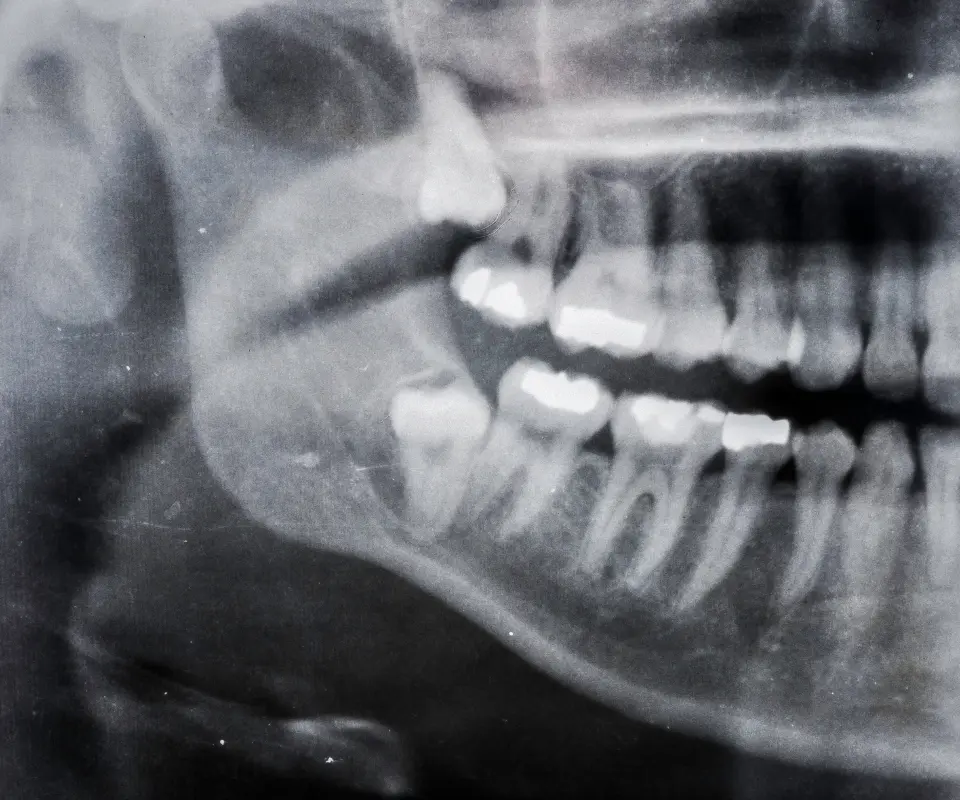

Swollen-Jaw-Treatment-Tucker-GA